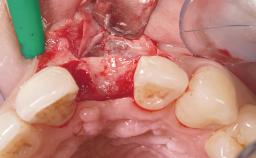

A 39-year-old male patient presented with a chief complaint of discomfort and gingival discoloration around his maxillary left central incisor. He was in good general health and was a non-smoker. His past dental history was significant because of the traumatic fracture of tooth 21 in a sporting accident at age 13. Initial dental treatment included endodontic therapy and a full-coverage restoration. The patient became symptomatic 5 years later, when structural failure of the tooth resulted in the dislodgment of the crown. Endodontic retreatment, apical surgery, and post-and-core restoration were performed.